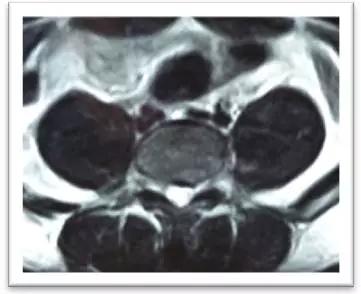

(術(shù)中)

4月8日,在局麻下,劉志安副院長親自實施了腰5/骶1椎間盤突出癥經(jīng)脊柱內(nèi)鏡髓核摘除術(shù),術(shù)中摘除了大塊脫出髓核組織。